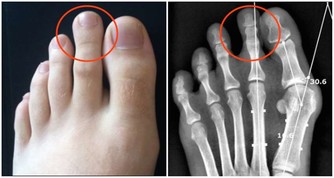

五、手部的警示信號

1、觀察自己的雙手,如果發現指尖比指節更粗大,可能是患有較嚴重的肺部疾病;